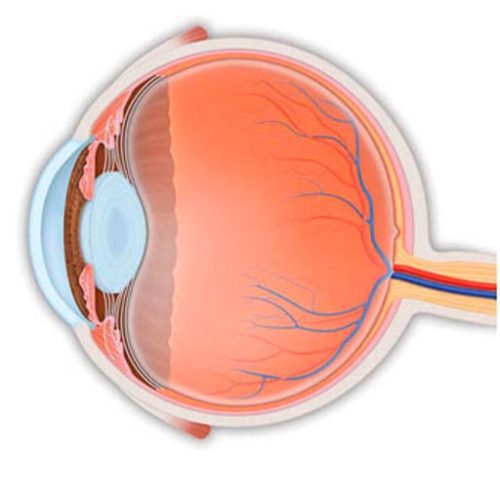

📍 Кости дают прочность.

📍 Суставы — гибкость.

📍 Мышцы — движение.

Если каркас ломается — рушится всё. От позвоночника до сердца, от суставов до дыхания. Восстановление этой системы = возвращение себе жизни в движении.